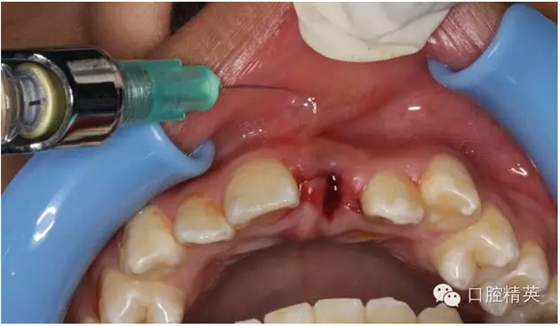

圖1.術(shù)前患者口內(nèi)像、牙槽窩輕度收縮、血凝塊穩(wěn)定、無滲出。

圖12.局部浸潤麻醉